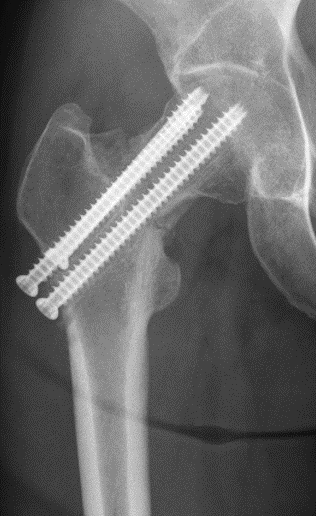

Pt has surgery at an outside hospital, where a surgeon performs a closed reduction and percutaneous screw placement, and is made non-weightbearing x 6 wks. Is this what you would do? How is the reduction? Which implant would you use? #OrthoTwitter #MedTwitter

8 wk follow-up xrays. Pt has persistent pain in the hip. What do you see? Is the fracture healing?

Pt has an impending femoral neck nonunion. She has varus collapse and shortening of the Fx. At this point, the Fx is unlikely to heal w/out intervention. Options include a total hip arthroplasty (THA) or a salvage procedure, namely a valgus intertrochanteric osteotomy.